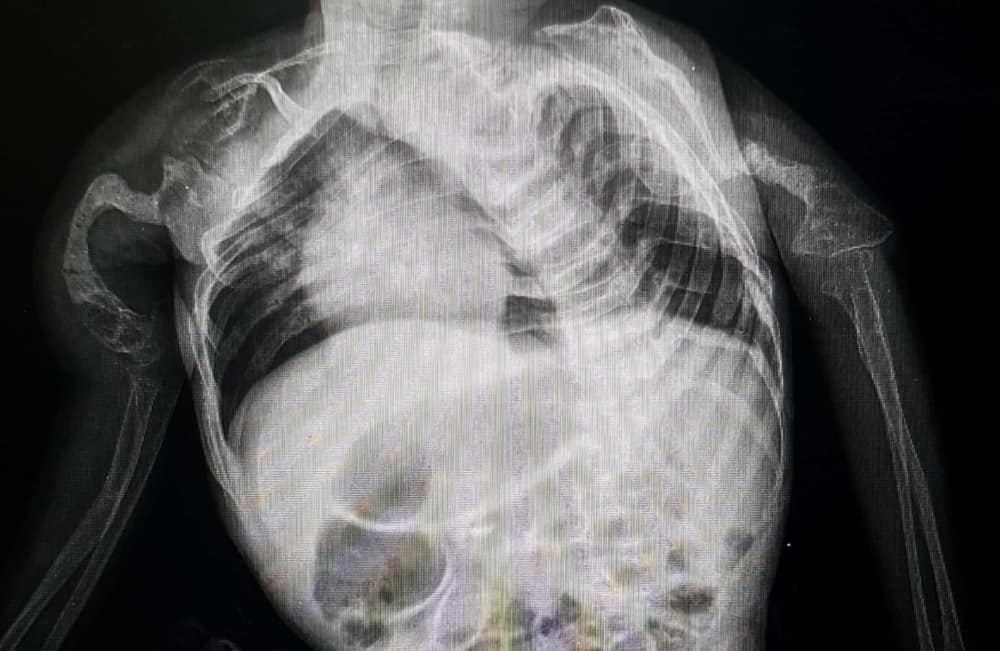

osteogenesis imperfecta

X-rays, DNA tests, blood or urine tests, and even biochemical testing help diagnose brittle bone disease in children. In severe cases, prenatal testing, such as an ultrasound, can identify broken bones and other bone deformities before a baby is born.